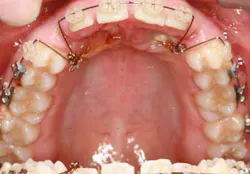

A ballista appliance was used to prevent a facial pull of the canines in order to avoid and prevent resorption of the roots of the lateral incisors. As movement progressed over the course of the next year, eruption of the canines was considered a success. Once in position, they will be pulled facially into occlusion.

The patient is pleased with the progress reached thus far and is ecstatic at the anticipation of a successful outcome.